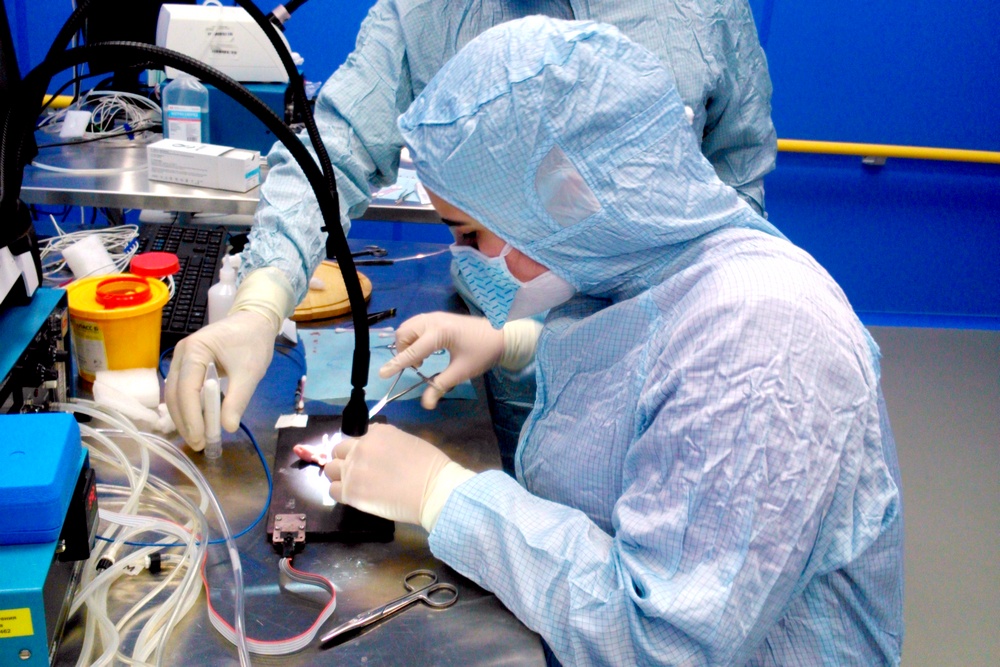

Мастер-класс по бариатрической хирургии и минимально-инвазивной колоректальной хирургии на крупных лабораторных животных (свиньях). |